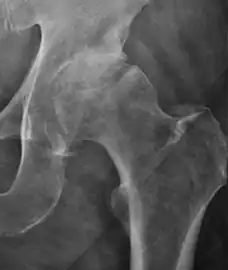

Radiological signs of transient osteoporosis of the hip include localized osteoporosis of the femoral head and neck (Figure 8). Nevertheless, final diagnosis has to be made with MRI to differentiate it from avascular necrosis and from insufficiency or stress fractures of the femoral head or neck. In case of AVN, radiographs can only demonstrate delayed or advanced signs. Staging according to Ficat classification ranges between normal appearance (stage I), slight increased density in the femoral head (stage II), subchondral collapse of the femoral head with or without “crescent” sign (stage III), and advanced collapse with secondary osteoarthritis (stage IV). In the case of stress or insufficiency fractures X-ray sensitivity has been proven to be much lower than MRI, which is currently the gold standard.[1]

Figure 8:

X-ray of a patient with transient osteoporosis of the left hip showing osteoporosis.[1]

Coronal stir imaging in transient osteoporosis, showing diffuse edema.[1]

Scintigraphy (A), sagittal T1 (B), and coronal PD fat sat of a patient with a subchondral fracture of the femoral head with convex shape to the articular surface.[1]

Coronal T1 of a patient with avascular necrosis of the femoral head.[1]